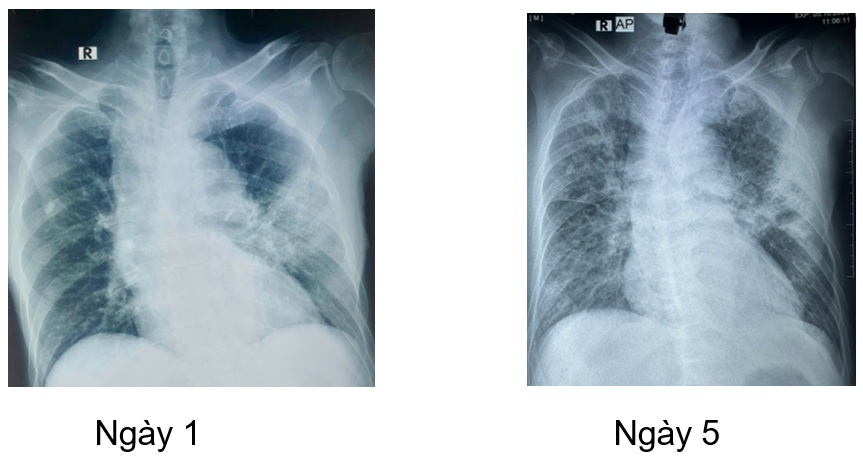

Bệnh nhân được tiếp tục duy trì phác đồ kháng nấm anidulafugin và fluconazole (hạ bậc kháng nấm), trong quá trình điều trị bệnh nhân được khám chuyên khoa mắt, theo dõi men gan, chức năng thận, bilan nhiễm trùng cũng như hình ảnh học (CTscan ngực, xquang ngực thẳng). Dưới đây một vài hình ảnh học trong quá trình điều trị nội, ngoại trú.